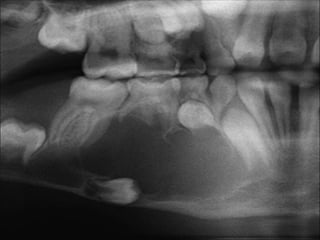

Case

 18 year-old female with several month history of lesion

Case  18 year-oldfemale with several month history of lesion in right maxilla, treated initially by oral surgeon with multiple curettage.  Has experienced recent onset of rapid expansion, with complaints of loose dentition and pain.